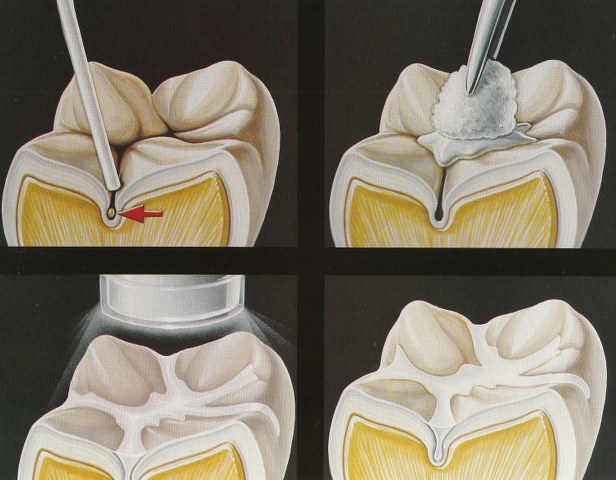

Sigillature dei solchi: cosa sono?

Continua